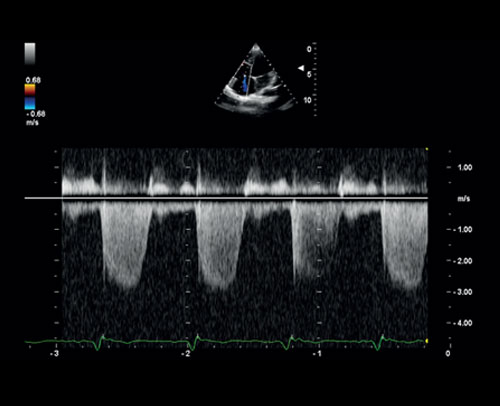

CW Doppler trikuspidální regurgitace.